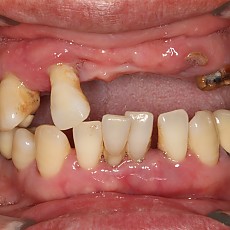

시술전후사진 2 페이지

Total 62건 2 페이지